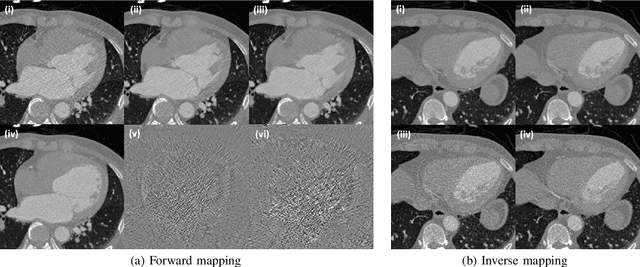

Recently, CycleGAN was shown to provide high-performance, ultra-fast denoising for low-dose X-ray computed tomography (CT) without the need for a paired training dataset. Although this was possible thanks to cycle consistency, CycleGAN requires two generators and two discriminators to enforce cycle consistency, demanding significant GPU resources and technical skills for training. A recent proposal of tunable CycleGAN with Adaptive Instance Normalization (AdaIN) alleviates the problem in part by using a single generator. However, two discriminators and an additional AdaIN code generator are still required for training. To solve this problem, here we present a novel cycle-free Cycle-GAN architecture, which consists of a single generator and a discriminator but still guarantees cycle consistency. The main innovation comes from the observation that the use of an invertible generator automatically fulfills the cycle consistency condition and eliminates the additional discriminator in the CycleGAN formulation. To make the invertible generator more effective, our network is implemented in the wavelet residual domain. Extensive experiments using various levels of low-dose CT images confirm that our method can significantly improve denoising performance using only 10% of learnable parameters and faster training time compared to the conventional CycleGAN.